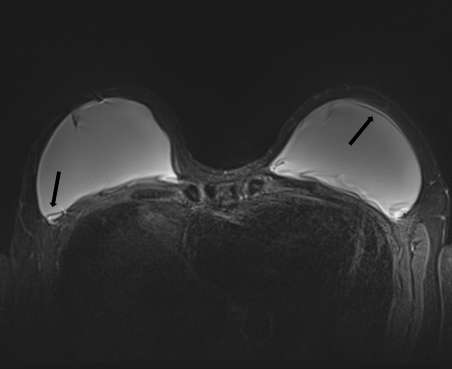

Fully collapsed intracapsular ruptures appear as multiple hypointense curvilinear lines that float within the hyperintense silicone gel, referred to as the “linguine sign” (Figure 4). The floating curvilinear lines represent the collapsed outer shell6.